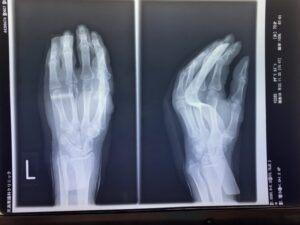

【橈骨遠位端骨折】コーレス骨折の治療とリハビリ|手術以外の選択肢と後遺症…